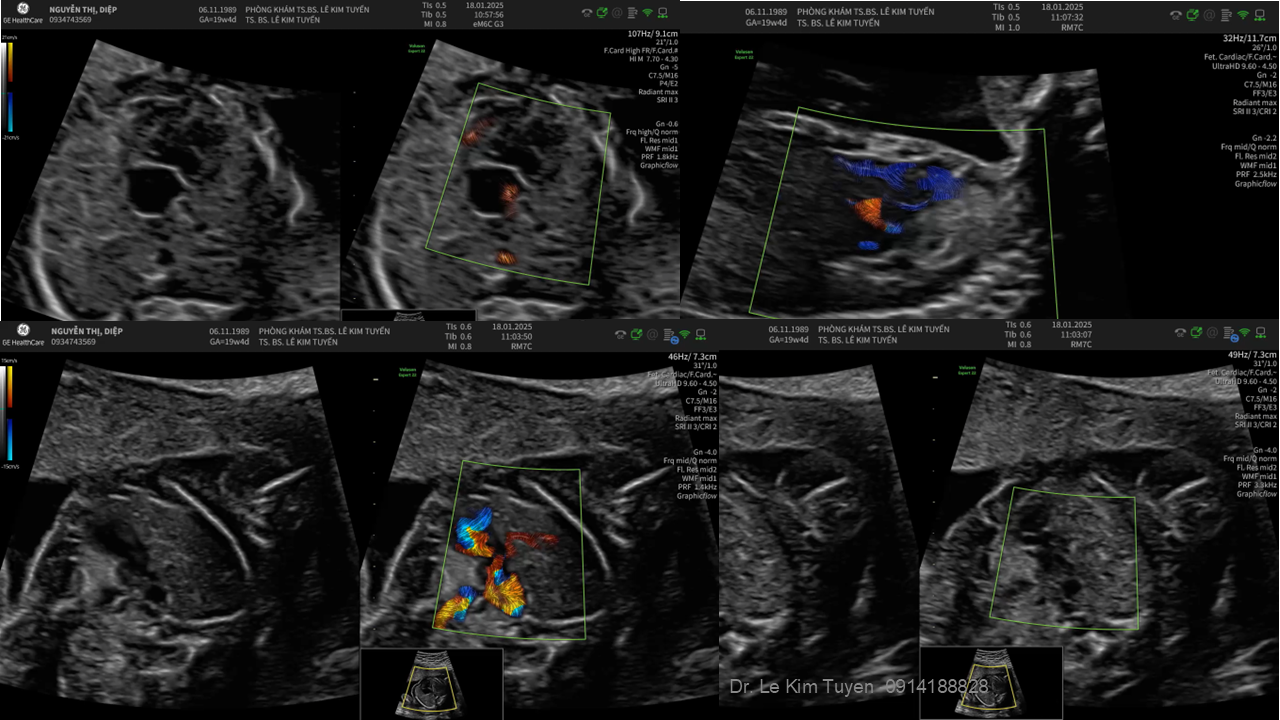

Áp dụng công nghệ Graphicflow trong phát hiện bệnh tim bẩm sinh cần cấp cứu sơ sinh

TS. BS. Lê Kim Tuyến

Bệnh viện Tim Tâm Đức